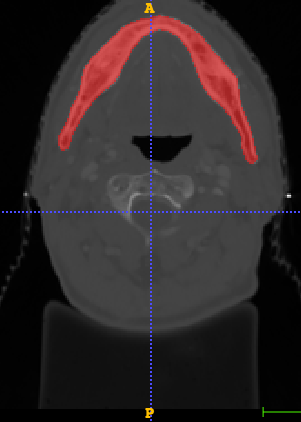

In Chapter 6, we propose an end-to-end, atlas-free 3D convolutional deep learning framework for fast and fully automated whole-volume HaN anatomy segmentation [115]. Our deep learning model, called AnatomyNet, segments OARs from head and neck CT images in an end-to-end fashion, receiving whole-volume HaN CT images as input and generating masks of all OARs of interest in one shot. AnatomyNet is built upon the popular 3D U-net architecture, but extends it in three important ways: 1) a new encoding scheme to allow auto-segmentation on whole-volume CT images instead of local patches or subsets of slices, 2) incorporating 3D squeeze-and-excitation residual blocks in encoding layers for better feature representation, and 3) a new loss function combining Dice scores and focal loss to facilitate the training of the neural model. These features are designed to address two main challenges in deep-learning-based HaN segmentation: a) segmenting small anatomies (i.e., optic chiasm and optic nerves) occupying only a few slices, and b) training with inconsistent data annotations with missing ground truth for some anatomical structures. We collect 261 HaN CT images to train AnatomyNet, and use MICCAI Head and Neck Auto Segmentation Challenge 2015 as a benchmark dataset to evaluate the performance of AnatomyNet. The objective is to segment nine anatomies: brain stem, chiasm, mandible, optic nerve left, optic nerve right, parotid gland left, parotid gland right, submandibular gland left, and submandibular gland right. Compared to previous state-of-the-art results from the MICCAI 2015 competition, AnatomyNet increases Dice similarity coefficient by 3.3% on average. AnatomyNet takes about 0.12 seconds to fully segment a head and neck CT image of dimension , significantly faster than previous methods. In addition, the model is able to process whole-volume CT images and delineate all OARs in one pass, requiring little pre- or post-processing. We demonstrate that our proposed model can improve segmentation accuracy and simplify the auto-segmentation pipeline. These contributions are released as an open-source software package called AnatomyNet, which is publicly available555https://github.com/wentaozhu/AnatomyNet-for-anatomical-segmentation. Portions of this chapter were published as part of [115].

- [121] W. Zhu and X. Xie. Adversarial deep structural networks for mammographic mass segmentation. arXiv:1612.05970, 2016.